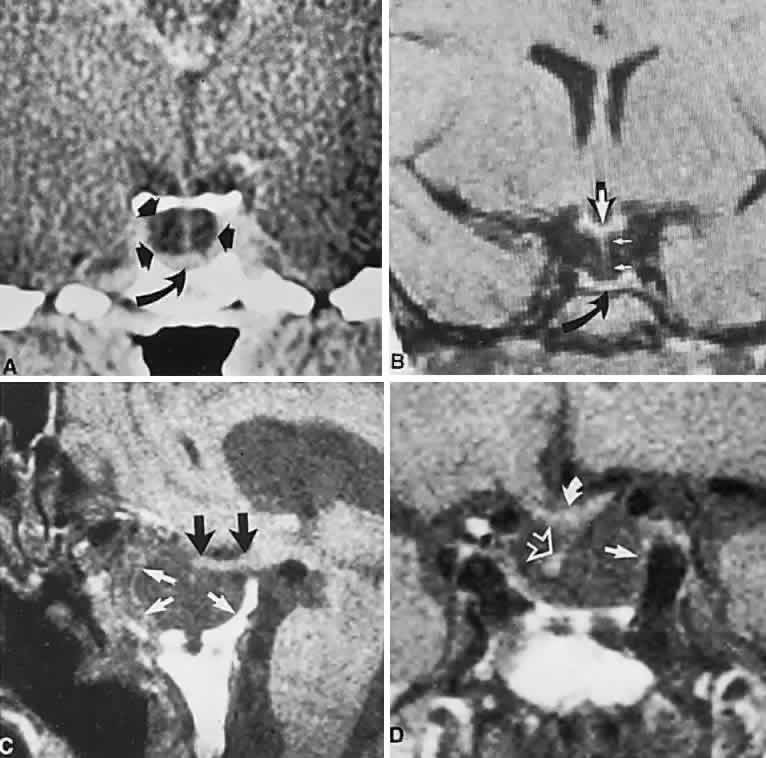

The absence of field defects, for example, in patients undergoing evaluation for amenorrhea, galactorrhea, or sellar enlargement incidentally discovered, does not imply the absence of an adenoma. Obviously, patients with microadenomas, that is, confined within the sella, do not have field defects. From a study24 of 50 cases of pituitary adenomas with chiasmal syndrome, it was concluded that visual disturbance occurs when the chiasm is displaced approximately 10 mm upward (see also Volume 2, Chapter 4, Fig. 6). The modern management of pituitary adenomas should involve several disciplines: current neuroradiologic studies detect microadenomas and provide precise delineation of gross morphology and status of neighboring structures, and mixed MRI signals suggest new or old hemorrhage, cysts, and so forth (Fig. 2); radioimmunoassay techniques assay PRL and other endocrine levels; oral neuropharmacologic agents, such as bromergocryptine, provide a “medical adenomectomy” for hyperprolactinemia and acromegaly; transsphenoidal surgery, including high-illumination microscopical procedures, televised radiofluoroscopic monitoring, and infection control, has all but replaced transcranial approaches; immunohistochemistry techniques have replaced the anachronistic tinctorial designations (e.g., chromophobe, basophilic) with a functional classification.

Fig. 2. Large prolactinoma. Original vision in the right eye (RE) was 8/200, left eye (LE) 1/200, with serum prolactin of 26,000 ng/ml and galactorrhea. Four months of bromocriptine reduced prolactin to 661 ng/ml, vision improved to RE 20/40, LE 20/50. At 3 years, vision was as follows: RE 20/30, LE 20/20; prolactin was 25.9 ng/ml. Enhanced magnetic resonance imaging. Sagittal (A) and coronal (C) images at diagnosis. Sagittal (B) and coronal (D) images at 2-year follow-up, showing dramatic shrinkage of the mass.

In addition to the radiologic implications mentioned previously, specific points should be emphasized. Contrast-enhanced CT and, especially, MRI have replaced all previous radiologic techniques in the detection and anatomic assessment of sellar and juxtasellar lesions. MRI has also the inherent advantage of using no radiation, nor does it require iodinated contrast injections. Although thin-section contrasted CT does indeed disclose most lesions, bone changes, and recent hemorrhage, MRI is superior in delineating distortions of optic nerves and chiasm, in displaying arteries, and in revealing fat, hemorrhage, or cyst (see Figs. 3E through M). Indeed, in a prospective study of normal volunteers, gadolinium-enhanced MRI disclosed pituitary adenomas (3 mm to 6 mm in diameter, i.e., microadenomas) in 10% of adults aged 18 to 60 years.66 T2-weighted fast spin-echo MRIs are currently the most precise sequence for demonstrating the optic nerves and chiasm, even when these structures are severely distorted by suprasellar tumor extension.67